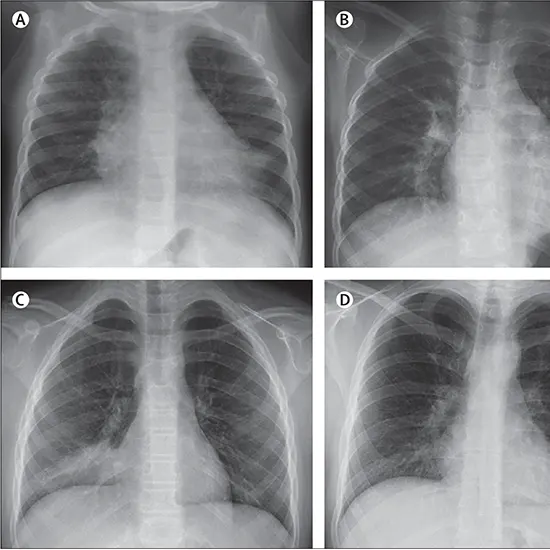

Diagnosis involves a physical examination, chest X-ray, blood tests, and sputum culture. Treatment usually includes rest, hydration, and over-the-counter medications. Antiviral medications may be prescribed, but only work within a few days of symptom onset. Antibiotics are not effective against viral infections.